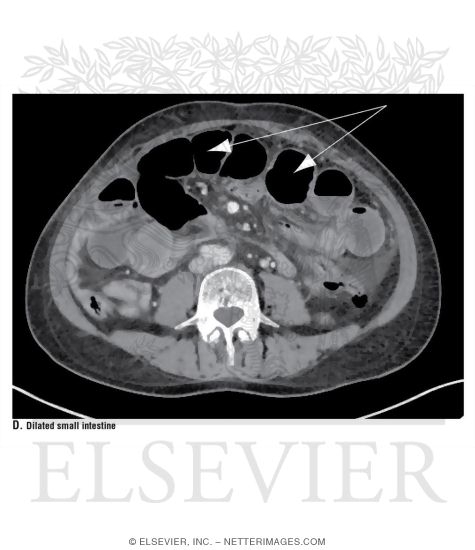

Dilated Small Intestine